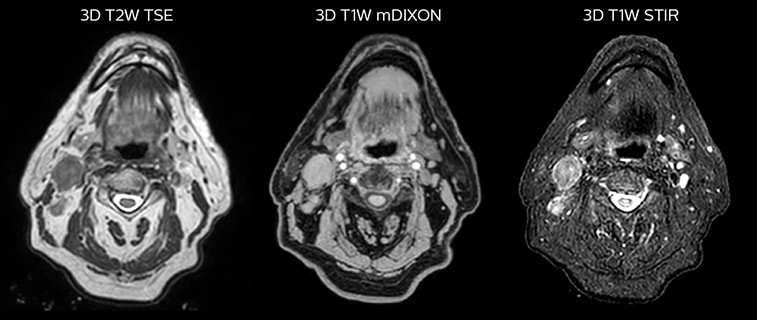

T2W 3D, 3D STIR and mDIXON MRI scans.

Epidermoid carcinoma of the left tongue base

The patient was diagnosed with an epidermoid carcinoma of the base of the left invading the amygdala lodge and the amygdaloglossal groove. Radiochemotherapy with curative aim was prescribed with a dose of 70 Gy for the tumor, 66 Gy on the suspicious nodes and 56 Gy on the elective drainage areas - in 33 fractions.